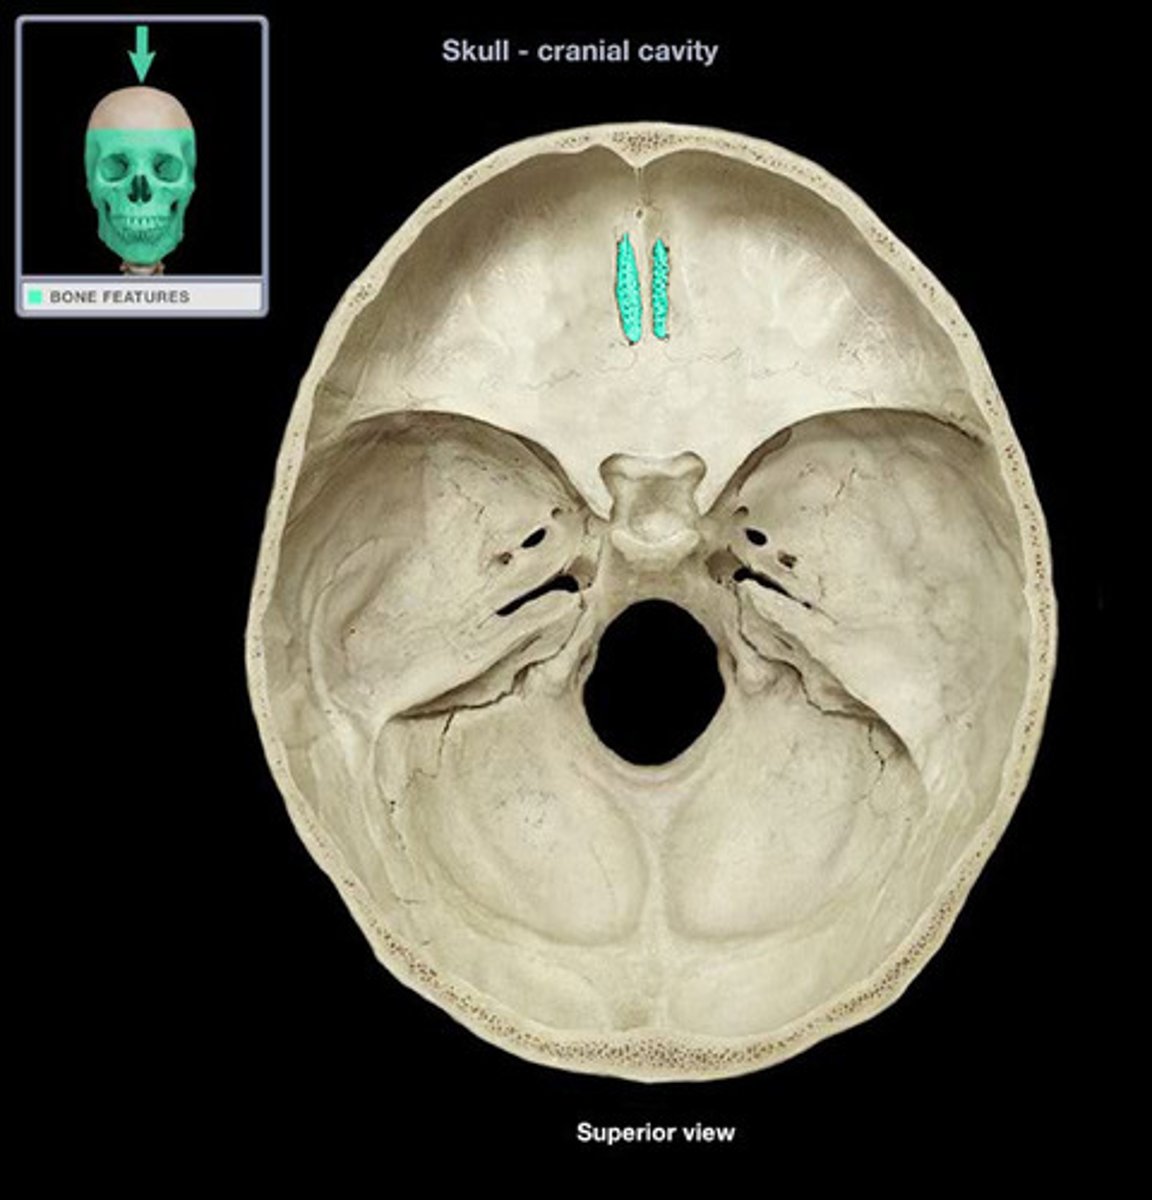

Cribiform Plate

Pituitary Fossa

Name the dip